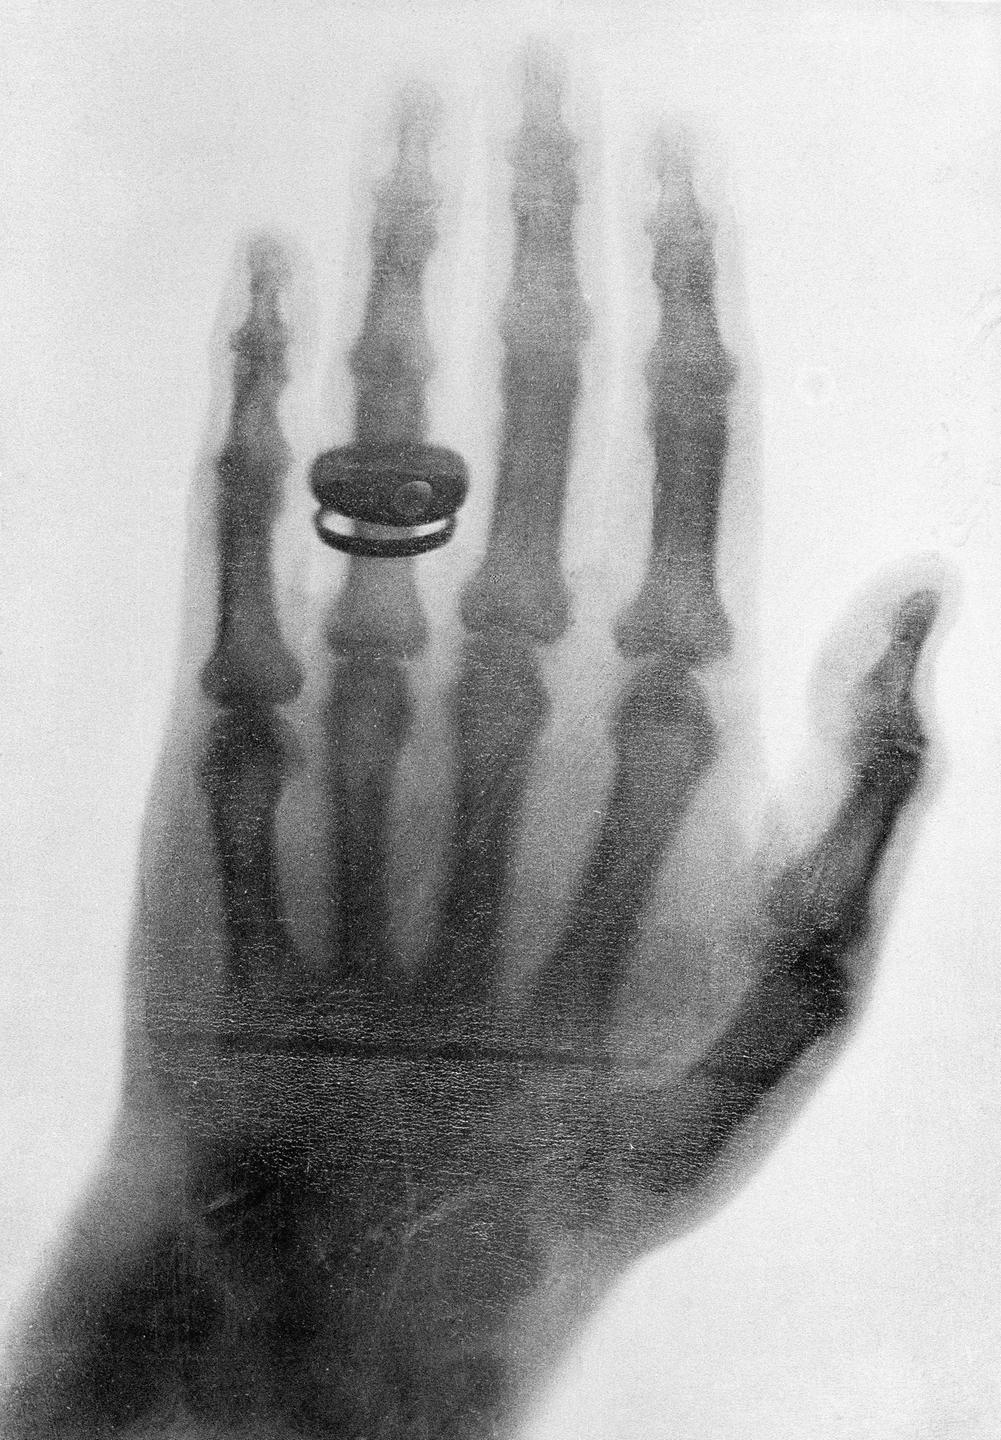

Wilhelm Conrad Röntgen war ein deutscher Physiker und Entdecker der nach ihm benannten Röntgenstrahlen. Er studierte Maschinenbau und Physik und wurde später Professor, unter anderem in Würzburg. 1895 machte er eine sensationelle Entdeckung: eine neue Art von Strahlen, mit denen man das Innere des menschlichen Körpers sichtbar machen konnte. Das erste berühmte Bild zeigte die Hand seiner Frau. Diese Entdeckung revolutionierte die Medizin und wird bis heute in der Diagnostik eingesetzt. 1901 erhielt Röntgen den ersten Nobelpreis für Physik. Er verzichtete darauf, seine Entdeckung patentieren zu lassen, weil sie der Allgemeinheit dienen sollte.